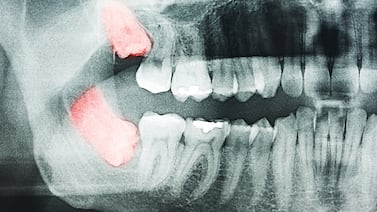

Quienes por alguna razón deben extraer sus cordales, últimas piezas dentales en salir, deben tener en cuenta algunas recomendaciones, que según los especialistas pueden hacer la diferencia entre una sana o traumática recuperación.

Si se deja pasar tiempo, bacterias infectarán la boca y el dolor será mayor